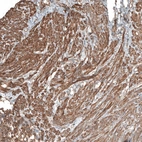

Immunohistochemical staining of human smooth muscle shows moderate positivity.